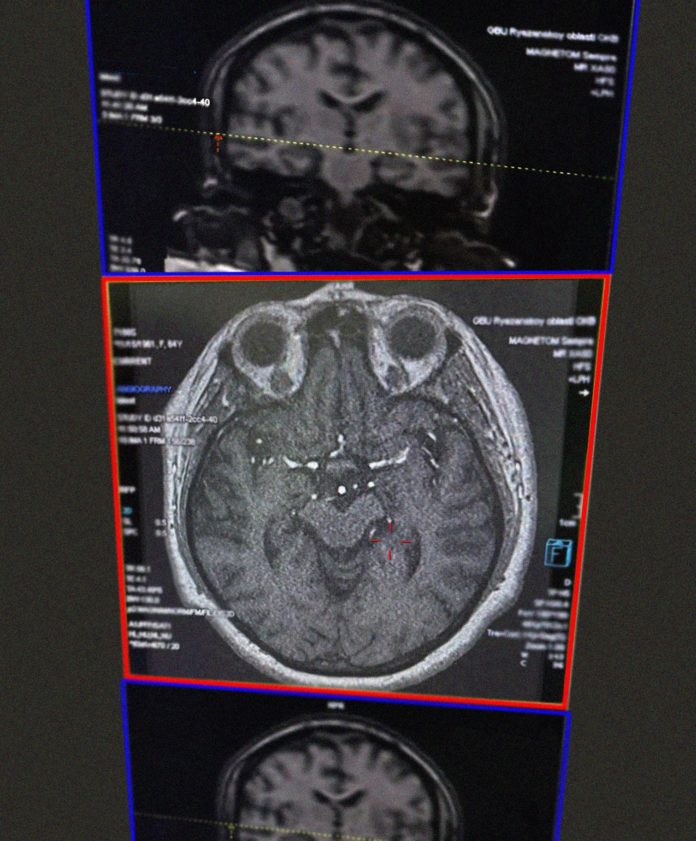

Пациентку доставили в ОКБ. При осмотре и сборе анамнеза диагноз подтвердился. Женщину экстренно начали готовить к процедуре тромболизиса. Об этом сообщается в группе медучреждения в соцсети.

Через 9 дней состояние пациентки улучшилось до удовлетворительного. Она уже могла практически самостоятельно передвигаться, а её речь постепенно восстанавливалась. Из беседы с женщиной выяснилось, что к сосудистой катастрофе привели вредные привычки: многолетнее курение и употребление жирной, жареной и пересоленной пищи. Это вызвало закупорку сосудов холестериновыми бляшками и резко нарушило кровоснабжение мозга.